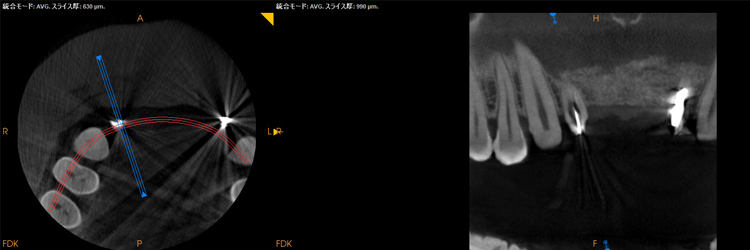

診査・診断・カウンセリング根管治療 を行なう歯の診査はいろいろあり、当院ではレントゲン撮影、CT撮影、触診、打診、神経の生活度の診査、歯周ポケット検査から歯の状態を診査します。個々の歯によって病気の状態は様々です。治療の難易度、予後、治療に伴うリスク、治療期間、費用などをご説明していきます。当院で治療を行う歯には、通常の二次元画像のレントゲンでは診断が難しい場合、または、治療にあたって歯根の形を詳細に把握し、根管の形に適したサイズの器具を選択するため、根管治療専用の高精細モードのCBCT 撮影を行うことがほとんです。 当院のCBCT は根管治療専用モードのため撮影範囲が最小です。インプラント用CTのような撮影範囲が大きい機種よりも被曝量が少なく、無駄な被曝がないよう配慮しています。 |

根管治療治療はラバーダムの装着を行い、根管治療中はマイクロスコープを常に使用した治療を行います。上の奥歯の治療ではよく見落とされている根管(MB2)があり、細菌の繁殖部位になり治らない原因になりますマイクロスープを使用しながら見逃されてしまった根管(MB2)を探索しているところMB2を発見し穴を広げたところ、殺菌がしっかり届くようになります |